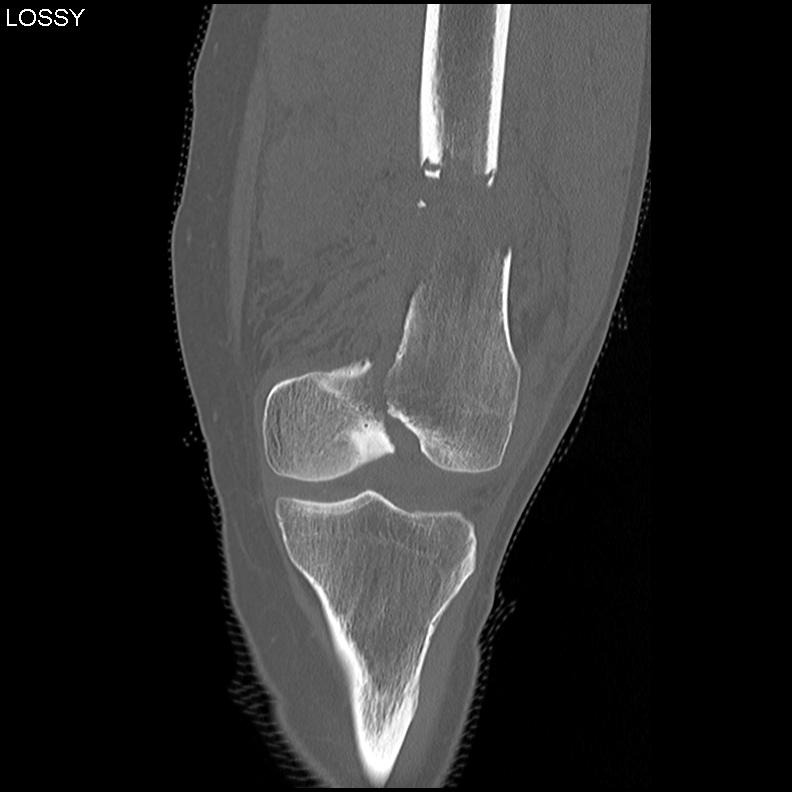

Type C: Complete articular

Xray / CT

Options

Dual Plate

Plate + Retrograde nail

Distal femur replacement